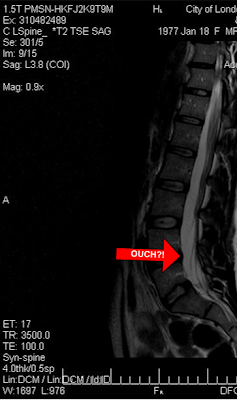

An MRI was suggested, so I once again benched myself, and I waited.

The radiologist's report claimed a normal result, which my sports med doc agreed with and suggested a few weeks of accupuncture. More than half of MRIs administered to people my age show disc issues that have no injury symptoms according to the doc, so it seems that a normal scan may just mean nothing extreme.

A few weeks in, I'm no better, and my physio, who is a spine specialist, is encouraging a second opinion because he and several of his colleagues think that the bump highlighted in the picture is the cause of my woes. That's where a disc appears to be pressing on my nerve.